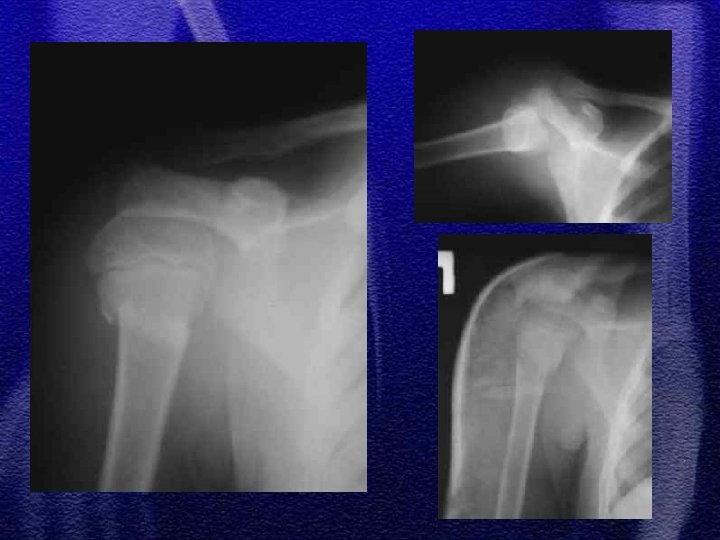

§ Najczęściej dotyczą trzonu § Złuszczenia nasad typ I lub II wg Saltera-Harrisa § Klasyczne urazowe zwichnięcia w stawie barkowoobojczykowym z uszkodzeniem więzadeł kruczo – barkowych występuje jedynie u dzieci starszych, bardzo rzadko

1. złamanie szyjki chirurgicznej (przynasady) 2. zwichnięcie barku występuje u dzieci wyjątkowo rzadko, w starszej grupie wiekowej 3. u dzieci młodszych złuszczenie typ I, u dzieci starszych typ II 4. leczenie: jednoczasowa repozycja zamknięta, wyciąg szkieletowy, leczenie operacyjne rzadko 5. istnieje bardzo duża możliwość przebudowy kości w tej okolicy